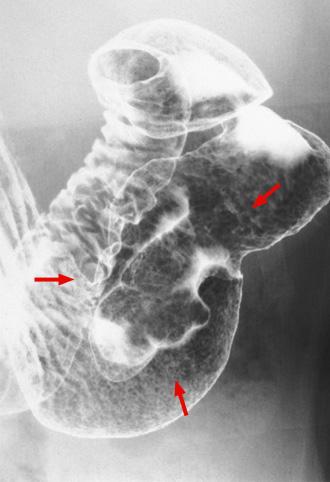

Hamartomatous inverted polyp(heterotopic gastric gland polyp)과 inflammatory fibroid polyp의 성상을 동반한 유경성의 위 융기성 병변

위(부위)/전정

X-P

30~34